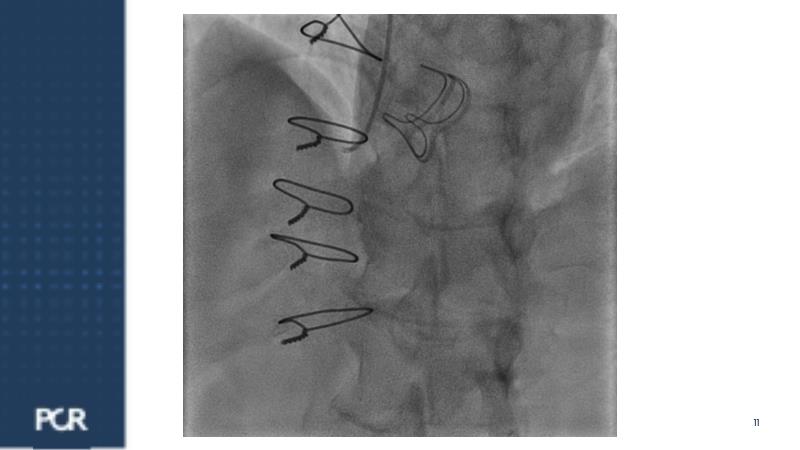

Watch this session focused on a patient with distal left main stenosis to understand that the stepwise provisional side branch (SB) stenting strategy is the standard approach for most left main trifurcation lesions. Discover the importance of optical frequency domain imaging for strategy determination and bifurcation PCI outcome optimization. Learn about the Ultimaster Nagomi™ DES, inheriting features from the Ultimaster Tansei™ stent, tailored for complex bifurcation anatomy with enhanced deliverability and overexpansion capacity.